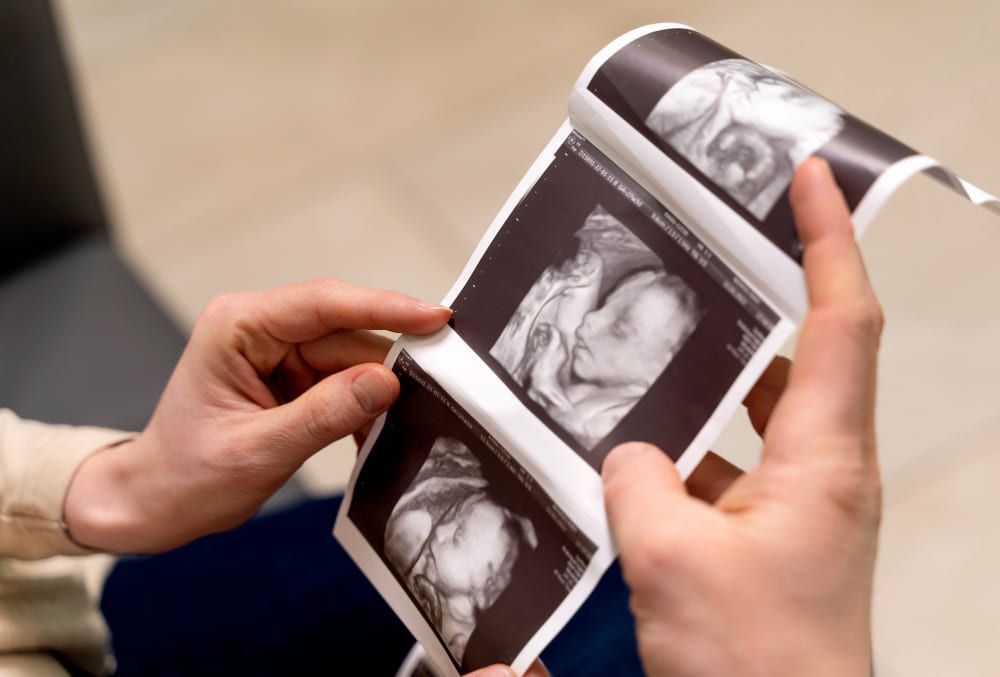

¿Quieres conocer cómo se está desarrollando tu bebé? La ecografía fetal es la solución perfecta para ti. Esta avanzada técnica médica utiliza ultrasonidos para garantizar el normal crecimiento fetal y detectar posibles anomalías. Con el avance de la tecnología, las ecografías 3D y 4D brindan imágenes más detalladas, permitiendo una mejor interpretación y un diagnóstico prenatal de alta precisión, ofreciéndote una visión clara del bienestar de tu bebé.

La ecografía fetal es un procedimiento médico que utiliza ultrasonidos para examinar el desarrollo del feto y detectar posibles anomalías o problemas durante el embarazo. En las últimas décadas, la tecnología ha avanzado, permitiendo obtener imágenes más detalladas y precisas, como las de las ecografías 3D y 4D.

Se utiliza ultrasonidos para crear imágenes del feto, evaluando su crecimiento y desarrollo. Con las ecografías en 3D y 4D, se obtienen imágenes detalladas del bebé, lo que permite detectar alteraciones físicas, malformaciones o problemas relacionados con la oxigenación o nutrición fetal.

Las ecografías 3D y 4D proporcionan imágenes detalladas de la cara, manos, pies y otras características del feto.

Las imágenes 3D y 4D permiten a los padres ver al bebé de manera más realista y cercana.

La ecografía fetal se realiza utilizando un ecógrafo que emite ondas de ultrasonido. Estas ondas rebotan en los tejidos del cuerpo y se capturan para formar una imagen. En las ecografías 3D y 4D, las imágenes obtenidas se procesan digitalmente para ofrecer una visión más completa y detallada del feto.

La ecografía fetal 3D y 4D es una técnica avanzada que permite visualizar el desarrollo fetal y detectar posibles anomalías durante el embarazo. Estas ecografías ofrecen imágenes detalladas que ayudan a garantizar el bienestar del bebé y de la madre. La Dra. Carolina Luque realiza estos estudios, proporcionando un diagnóstico preciso y entregando las imágenes en formato digital o en papel para que los padres puedan conservar este especial recuerdo.